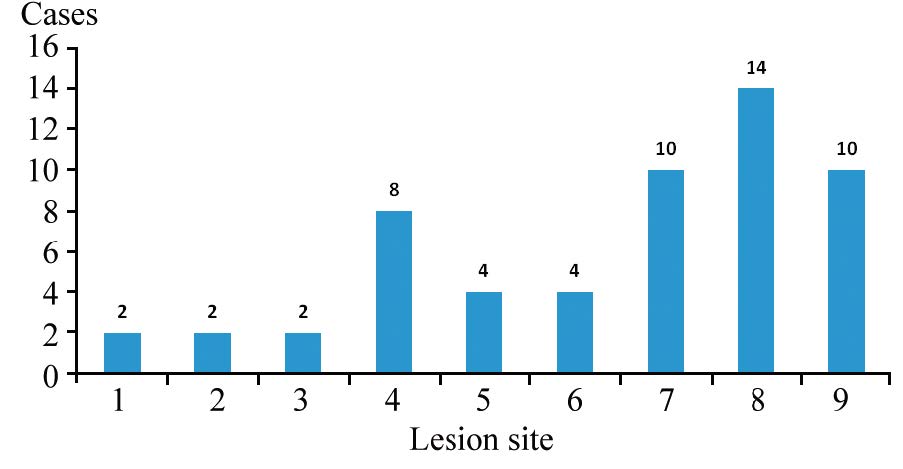

ResultsOf all 56 cases, there were twocases of local recurrence, 30 cases of metastasis, 14 cases without recurrence and 10 cases of second primarytumor. 18F-FDG PET/CT imaging was positive in 41 cases (one false positive case), negative in 15 cases (twofalse negative cases). The diagnostic efficiency of 18F-FDG PET/CT were: sensitivity 95.24%, specificity92.86%, accuracy 94.64%, false negative rate 4.76%, false positive rate 7.14%, positive predictive value(PPV) 97.56%, and negative predictive value (NPV) 86.67%. The PPV of increased CEA alone, increasedCA153 alone and their combination were 57.14%, 90.91% and 94.12%, respectively (χ2=10.430, P=0.005).

Conclusion18F-FDG PET/CT can be used to identify or rule out the recurrence and metastasis in breastcancer patients with increased serum CA153 and(or) CEA after treatment, with high diagnostic efficiency andgood clinical application value. And it can also suggest the second primary tumor.